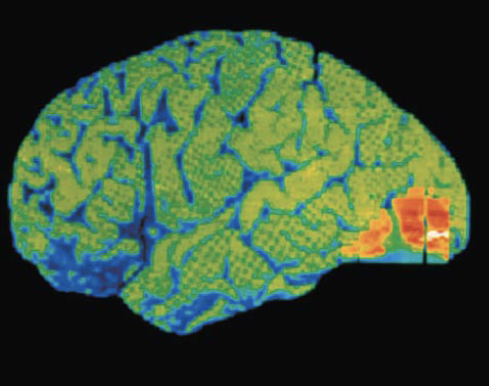

Functional imaging (PET and MRI) of brain show specific motor and sensory functions are located in discrete cortical areas called domains

Cerebral Cortex

Motor areas

Located in frontal lobe, motor areas act to control voluntary movement

Primary (somatic) motor cortex

Located in precentral gyrus of frontal lobe

Pyramidal cells: large neurons that allow conscious control of precise, skilled, skeletal muscle movements

Pyramidal (corticospinal) tracts: formed from long axons that project down spinal cord

Somatotopy: all muscles of body can be mapped to area on primary motor cortex